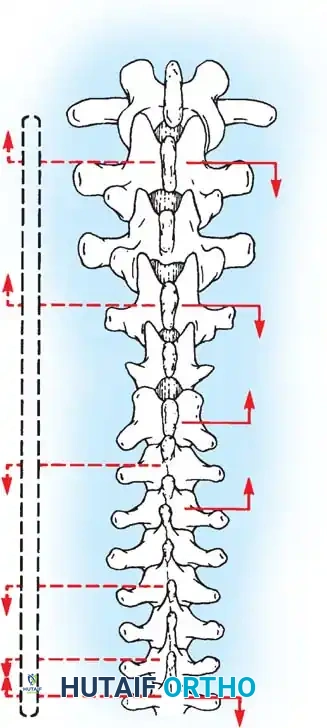

Fig. 38-26: The Moe technique of thoracic facet fusion, demonstrating the creation of hinged bone flaps.

- Expose the spine fully to the tips of the transverse processes.

- Using a sharp osteotome or Cobb gouge, begin a cut over the cephalad articular process at the base of the lamina.

- Carry this cut along the transverse process almost to its tip. Bend this cortical fragment laterally so it lies between the transverse processes, ideally leaving it hinged on its lateral periosteal attachment to preserve local vascularity.

- Thoroughly denude all articular cartilage from the superior articular process using a sharp curet.

- Make a secondary cut in the superior articular facet, working medially to laterally, producing another hinged fragment.

- Pack the resulting intra-articular defect tightly with cancellous bone graft.

The Moe Technique (Lumbar Spine)

In the lumbar spine, the facet joints are oriented in a more sagittal plane, necessitating a modified approach.

Fig. 38-27: The Moe technique adapted for lumbar facet fusion, addressing the sagittal orientation of the joints.

- Utilize a small osteotome or a needle-nose rongeur to resect the adjoining joint surfaces.

- This creates a distinct rectangular defect within the sagittally oriented joint space.

- Pack this defect forcefully with cancellous bone graft.

- Proceed to decorticate the entire exposed posterior elements (laminae and transverse processes) using Cobb gouges, always directing force away from the spinal canal.